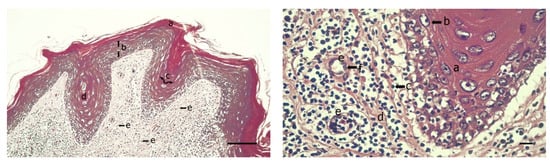

3.3. Histopathology